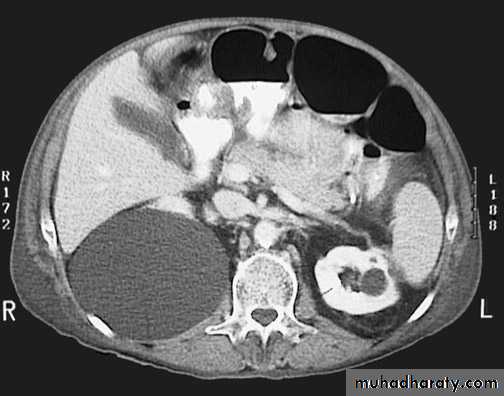

found in 1:1000 necropsies an is commoner in men.probably the most common of all renal fusion anomalies

The anomaly consists of two distinct renal masses lying

vertically on either side of the midline and connected at

their respective lower poles by a parenchymatous or fibrous

isthmus that crosses the midplane of the body.

Fusion of the renal masses early in embryonic life, so its ascent

will be impeded by inferior mesenteric artery.

The kidneys are low located, mal rotated and pelves lie anteriorly

Symptom When present, they are related to complications like hydronephrosis, infection, or calculus formation

Diagnosis ultrasound, IVU, CT scan